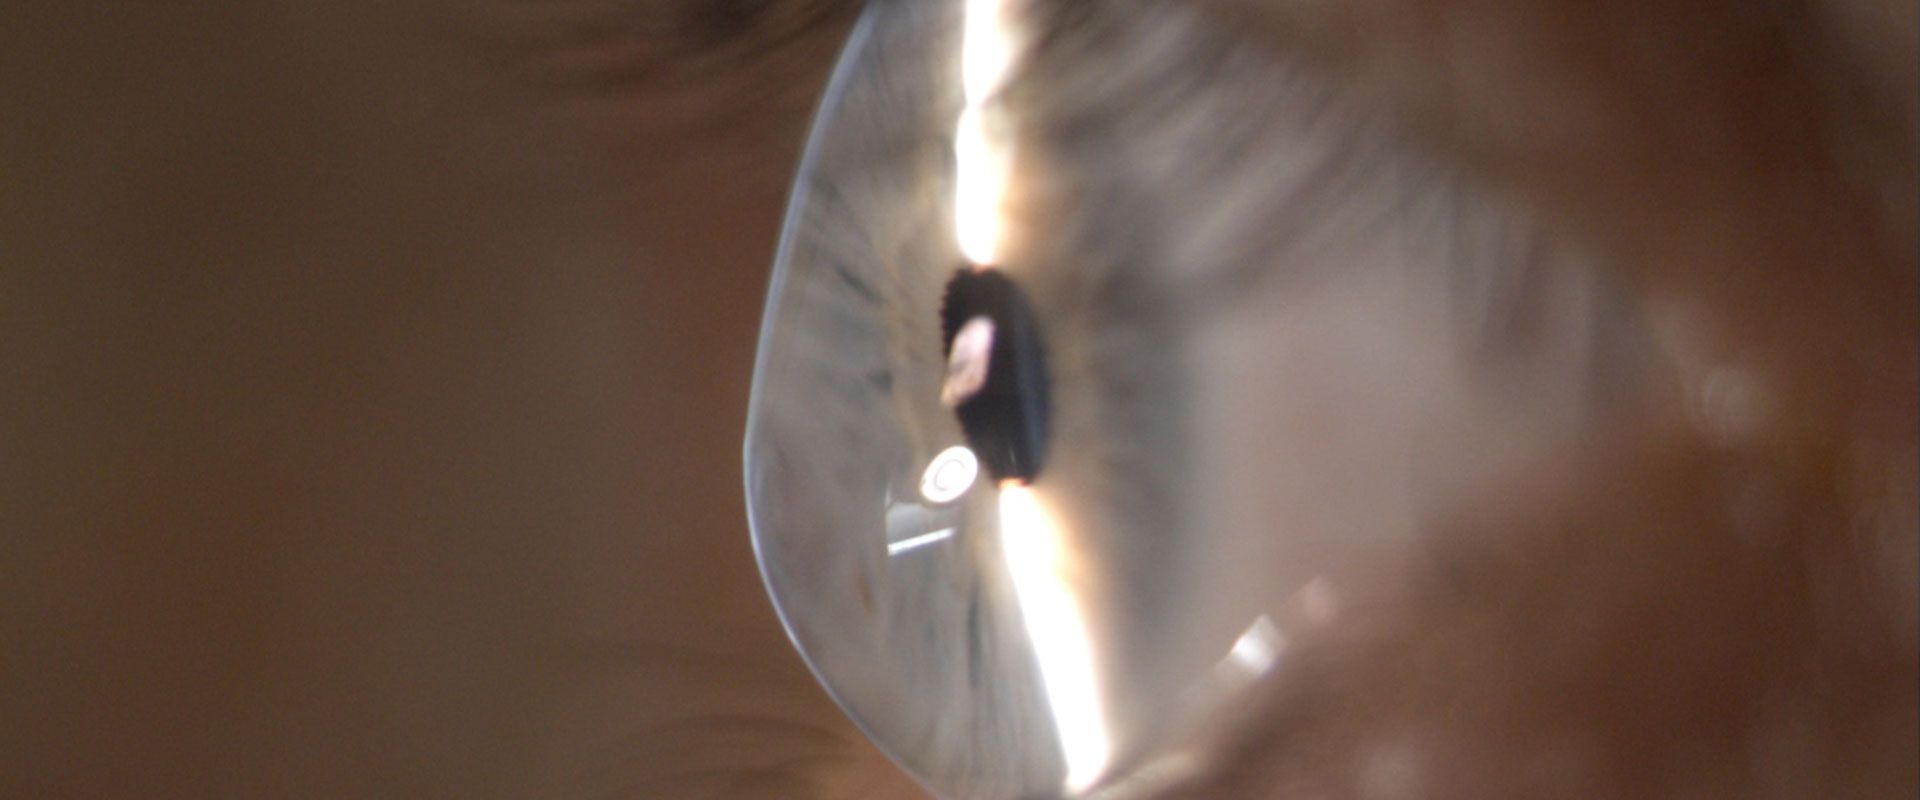

The fibres that make up the middle layer of the cornea (the transparent part of the eye) are weaker than normal, which causes the cornea to bulge and become distorted. Vision loses its sharp focus and reading and driving become difficult.

For some people it remains mild, but for others the progression advances to a stage where the cornea is very steeply curved and distorted. In about 2% of cases the back surface of the cornea splits, and the cornea becomes waterlogged and opaque. This is known as Hydrops – it can be painful but usually heals with time.